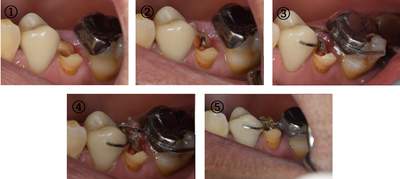

MTM開始直後と、終了後です。フックの位置が変わっているのがわかると思いますが、それが歯が動いた証拠となります。

MTM中。頬側には審美面の回復のために仮歯がついています。

歯からはフック、隣り合った歯にはワイヤーが渡してあります。そこにゴムをひっかけて歯を挺出させます。